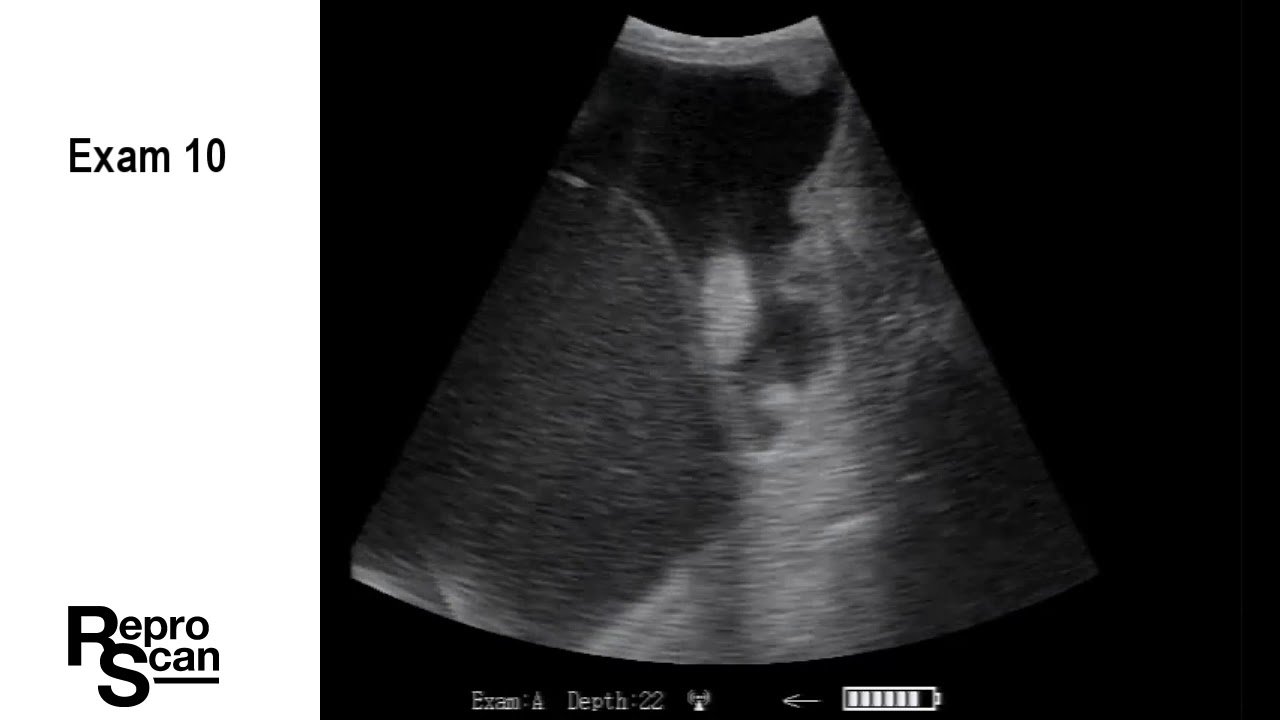

ReproScan Ultrasound Training - Separating A.I. Pregnancies from Bull Breds

This video gives people tips on how and when to ultrasound cattle so they can separate A.I. bred cattle from bull bred cattle. The images in the video were collected using a ReproScan XTC with an extension arm.